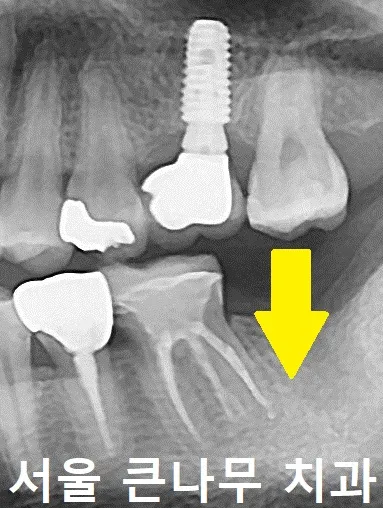

처음 오셨을 때의 사진인데요, 왼쪽 아래 맨 끝 어금니의 부재로 위에 치아가 밑으로 내려와 있는 상태를 확인할 수 있습니다.

실제 모습을 봤을 때 치아가 많이 내려왔다는 거 잘 보이시나요?

문제점을 해결하기 위해 우선 아래에 임플란트를 심었고, 위에 치아는 위로 끌어당겨주는 부분 교정에 들어가기로 하였습니다.